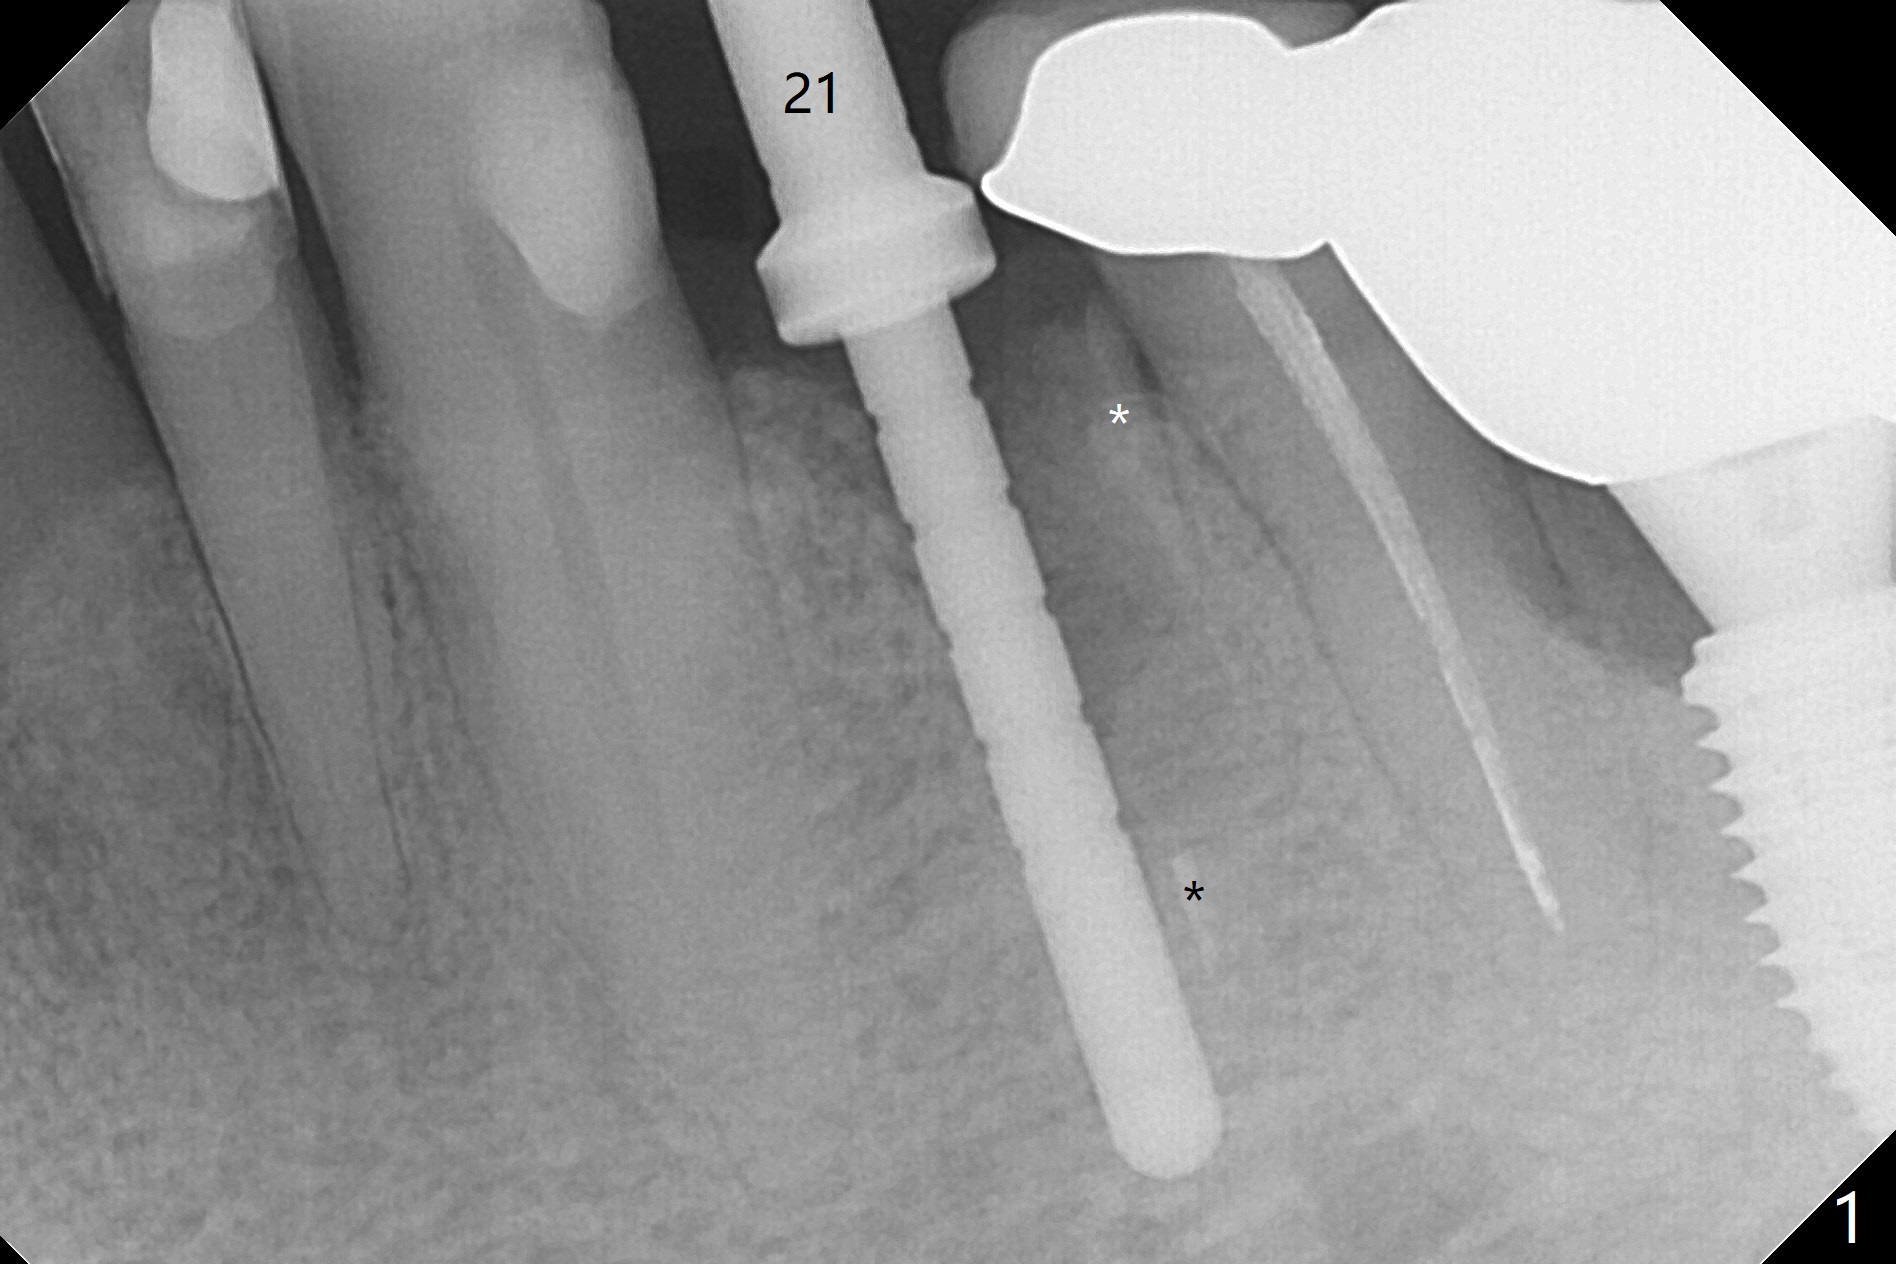

Extraction of the fractured tooth at #21 is as difficult as #19 (requiring incision). Because of the long root and hemorrhage, the apex of the tooth (Fig.1 black *) and a thin layer of the buccal shield (white *) remain when osteotomy is initiated. Due to hard bone, a 3.8x11.5 mm implant achieves insertion torque of ~35 Ncm (Fig.2); with placement of a 4.5x4(3) mm abutment, an immediate provisional is fabricated. There is limited remaining space for bone graft. The patient will return for final restoration 4 months postop; the buccal plate will be expected to have not collapsed! The implant seems to be osteointegrated, while the root piece (socket shield *) is exposed 4 months postop (Fig.3). The socket shield seems to be harmless, difficult to trim without local anesthesia and associated with no buccal plate concavity (Fig.4,5 <). With socket shield at #21, the crown looks normal, whereas the one at #19 without socket shield looks long, suggesting vertical bone loss early postop (before restoration, Fig.6).没有牙根处,角化龈少(图七,与术前(图八)对比)。